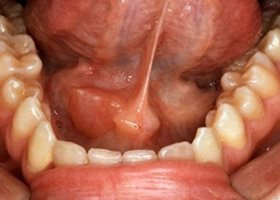

- Воспаление подъязычной слюнной железы – этот воспалительный процесс также известен как сублингвит.

Если возникает сиалоаденит подъязычной слюнной железы, симптомы будут схожи. Устье протоков железы может покраснеть и отекать. Болевые ощущения могут быть более выраженными, чем при подчелюстном сиалоадените.